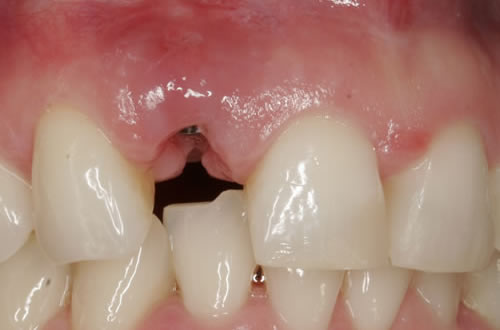

Eine besondere Herausforderung ist die Oberkieferfrontzahnregion. Der Wunsch nach einem perfekten Resultat ist geradezu selbstverständlich. Jeder möchte große, weiße Zähne und ein gesundes, reizloses Zahnfleisch besitzen (Abb. 3.30).

Abb. 3.30: Perfektes Resultat einer Versorgung.

7.4. Weichgewebsersatz

Häufig führt ein Zahnverlust zu einem Verlust von Knochen (Hartgewebe) und der bedeckenden Schleimhaut (Weichgewebe). Besonders im sichtbaren ästhetisch sensiblen Bereich ist es aber notwendig, dass sowohl Hart- als auch Weichgewebe so wiederhergestellt wird, dass im Idealfall das Zahnimplantat mit seiner Krone dem Aussehen des ehemaligen gesunden Zahn entspricht. Als Erfolgskriterien werden aus zahntechnischer Sicht die Form, Farbe und Größe der individuellen Krone angesehen. Aus medizinischer Sicht gibt es wichtige Erfolgskriterien, die die Implantatposition, die Implantatlänge, den Implantatdurchmesser, den Zahnfleischrand im Vergleich zum Nachbarzahn und die Zahnfleischpapillen zwischen den Zähnen beinhalten. Zusätzlich braucht man ein zahntechnisches Labor, das mit der Keramikverarbeitung ein natürliches Aussehen gestalten kann. Nur, wenn alle Parameter perfekt sind, ist das Ergebnis perfekt. Das macht den Einzelzahnersatz im Oberkieferfrontzahngebiet zu einer echten Herausforderung.

Nach der Entfernung von Zähnen kommt es schnell zu Knochenverlust (Resorptionen) und entsprechendem Verlust von Schleimhaut. Die Schleimhaut kann durch bestimmte Operationstechniken wiederhergestellt werden, in dem man freie oder gestielte Bindegewebstransplantate z. B. vom Gaumen entnimmt und das fehlende Material so ersetzt. Das Weichgewebe kann in unterschiedlichen Behandlungsphasen korrigiert werden. In vielen Fällen wird es während der Implantation oder bei der Freilegung verbessert. Manchmal müssen Feinkorrekturen auch nach Eingliederung der fertig gestellten Krone erfolgen, wenn ästhetische Einbußen vorliegen. Häufig hat die Zahnfleischkorrektur auch noch einmal die Änderung der endgültigen Krone zur Folge (Abb. 7.14, 7.15).